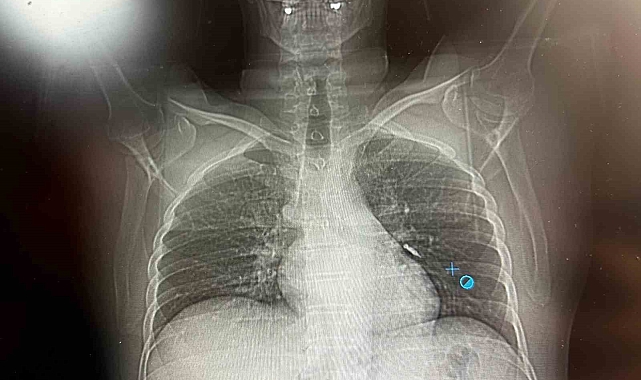

Op. Dr. Sadullah Aksoy, konuyla ilgili yaptığı açıklamada, hastanın ilk olarak hastanenin ek hizmet binasında çekilen tomografisinde vidanın sol akciğerin hava yollarının yaklaşık dördüncü dalına kadar ilerlediğinin tespit edildiğini belirtti. Acil bronkoskopi planıyla hastanın kabul edildiğini ve genel durumunun iyi olduğunu ifade eden Aksoy, "Bronkoskopi sırasında, implant vidasının sol üst lobun anterior segment bronşuna saplanmış pozisyonda olduğunu gördük. Üroloji bölümünde taş çıkarma işlemlerinde kullanılan cihazla müdahale ettik. İlk denemede implant tamamen çıkarılamadı ancak yerinden oynatılabildi. İşlem yaklaşık 3,5-4 saat sürdü." dedi.

Operasyon sonrası hastanın şiddetli bir öksürük geçirdiğini ve bu öksürükle birlikte implant vidasını midesine gönderdiğini anlatan Aksoy, yapılan kontrol akciğer filminde vidanın görünmediğini ve toraks ile batın BT (bilgisayarlı tomografi) görüntülemesinde ise implantın akciğerden çıktığı ve vücutta herhangi bir yerde bulunmadığı tespit edildiğini ekledi. Vida, daha sonra doğal yollarla vücuttan atıldı.